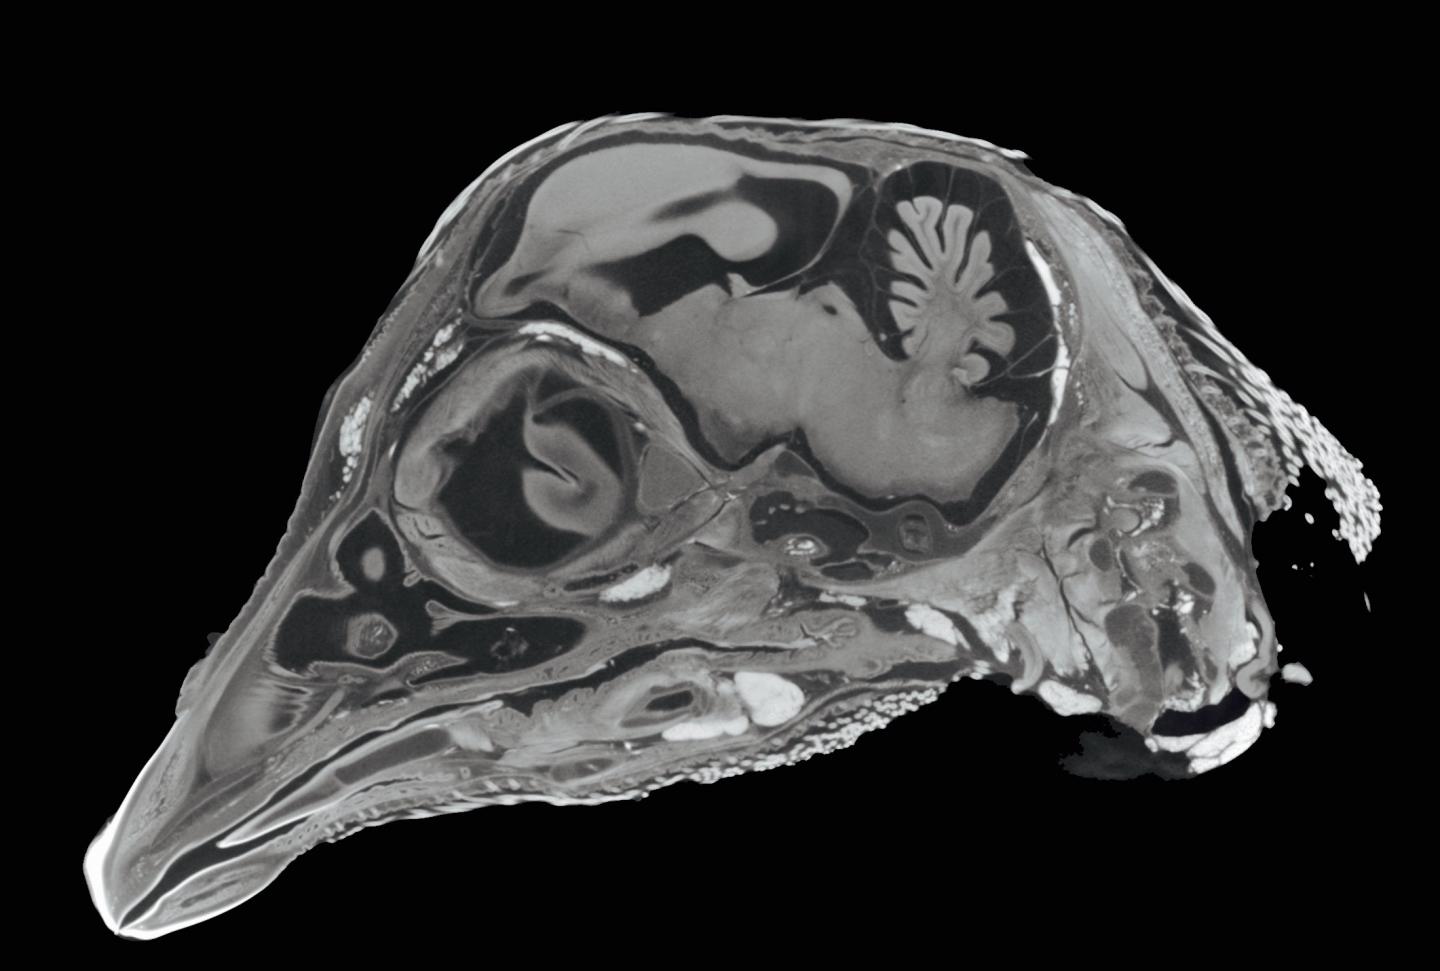

Using x-ray imaging technology similar to the CAT scans found in hospitals, micro-CT scanners allow an object's internal spaces to be visible at the microscopic level, and recreate virtual 3-D models without dissection, which is damaging to the original specimen. With this capability, Hoffmann and her anatomy colleagues will soon view the internal morphology of fossils, measure bone density, map the internal structure of the brain, and closely examine intricate vessels and other soft tissue structures - tasks that would have previously required dissection.